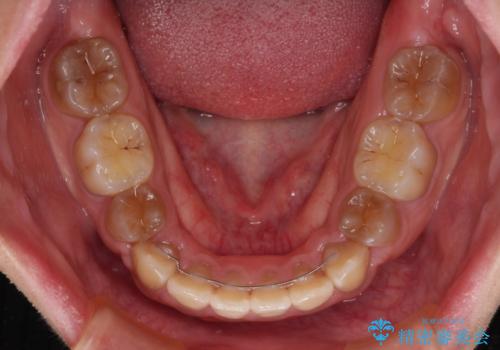

4本の歯を抜歯したことで、飛び出していた口元が引っ込み、横顔が大きく改善されました。